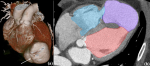

Diagnostic assessment: transthoracic echocardiography revealed a large apical pseudoaneurysm (6.6 × 8.1 cm) and a 1.2 cm post-infarction ventricular septal defect (PI-VSD) with predominantly left-to-right shunting. Left ventricular ejection fraction (LVEF) was 26%, with pulmonary hypertension (rSPAP 76 mmHg) (Figure 1). Cardiac computed tomography angiography (CCTA) confirmed a 7.1 × 8.1 cm pseudoaneurysm communicating with both ventricles, chamber dilation, RV hypertrophy, and moderate pericardial effusion (Figure 2). Follow-up coronary angiography and ventriculography showed persistent proximal and mid-LAD stenosis (85-90%), 40% mid-distal Cx stenosis (TIMI III), and unobstructed RCA (TIMI III). Left ventriculography revealed a pseudoaneurysm measuring 92 × 73 × 81 mm with hypokinesia of the anterior, anteroseptal, and lateral walls; EDV 221 mL, ESV 79 mL, EF 65%. Electrocardiography demonstrated sinus rhythm, HR 83 bpm, pathological Q waves in V1-V6, flattened T waves in I, II, III, aVL, aVF, and persistent ST-segment elevation in V2-V5, consistent with prior anterior MI. High-sensitivity troponin T was 25.3 ng/mL. Laboratory assessment revealed elevated cardiac troponin, systemic inflammation (increased CRP levels), mild hepatic enzyme elevation, moderate renal impairment (CKD C3a), and subclinical hyperthyroxinemia.

Figure 1: echocardiogram, 4-chamber view showing pseudoaneurysm (*) communicating with the left ventricle (LV), right ventricle (RV)